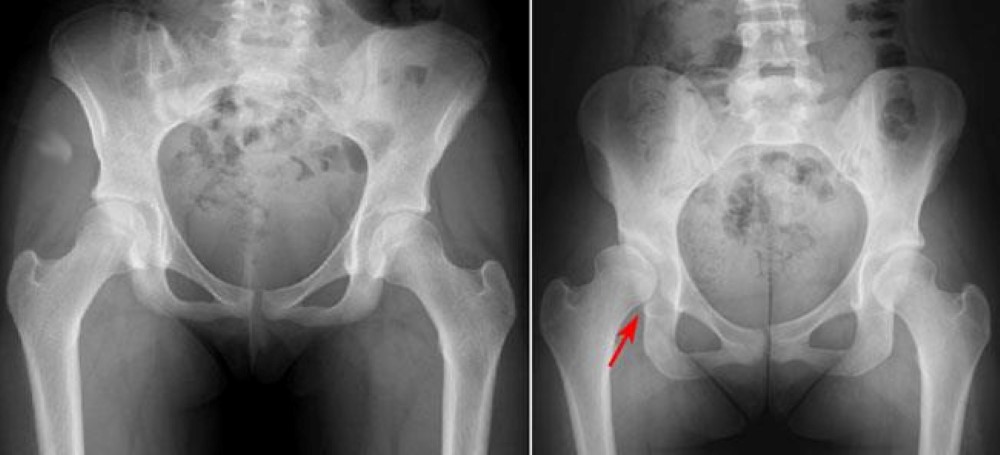

Orthopaedic surgeons specialising in adult hip reconstruction surgery often face the problem of osteoarthritis secondary to congenital hip disease CHD. The first type is dysplasia in which the femoral head is contained within the original true acetabulum. We describe three distinct types of congenital hip disease in adults.

A C The Three Main Types Of Congenital Hip Disease In Adults Are A Download Scientific Diagram

Understanding the classi cation of CHD in dysplasia low dislocation and high dislocation and being informed of the natural history of each type is crucial for the manage-ment of the disease for which in recent years total hip replacement THR has been the main approach.

Congenital hip disease in adults. Osteoarthritis of the hip is a disease which wears away the cartilage between the femoral head and the. We describe three distinct types of congenital hip disease in adults. Thats the report from Italian orthopedic surgeons on 32 hip replacements. Unlike osteoarthritis which is a wear and tear phenomenon rheumatoid arthritis is a chronic. Understanding the classi cation of CHD in dysplasia low dislocation and high dislocation and being informed of the natural history of each type is crucial for the manage-ment of the disease for which in recent years total hip replacement THR has been the main approach. Thats the report from Italian orthopedic surgeons on 32 hip replacements. Classical hinged abduction is well known and is thought to be responsible for secondary lateral. This disease is called developmental dysplasia of the hip joint DDH and dysplasia here refers to a disorder in the natural growth and development of the hip joint.